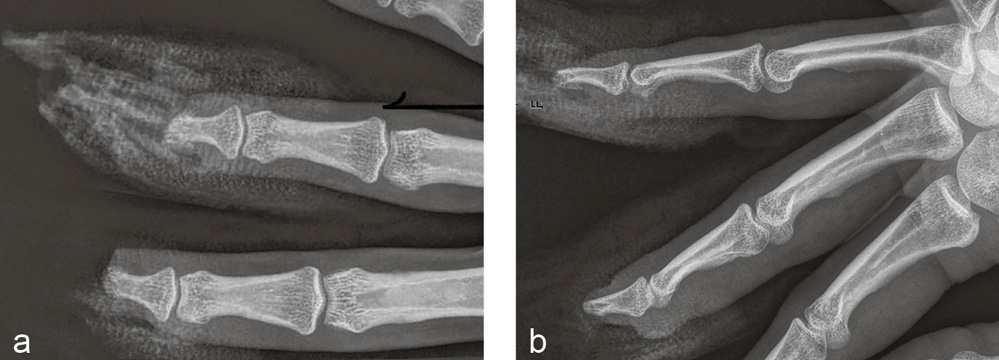

Diagnostik: Röntgenaufnahme rechter Mittel- und Ringfinger: Verlust des Nagelkranzes an beiden Fingern (Abbildung 10 a, b).

Abbildung 10 a und b: Röntgenaufnahme des dritten und vierten Fingers rechts in zwei Ebenen vom Unfalltag: Verlust des Nagelkranzes an beiden Fingern.